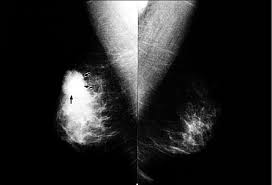

What Does Inflammatory Breast Cancer Look Like / Pathology Of Inflammatory Breast Cancer Springerlink - Like other types of breast cancer, inflammatory breast cancer can occur in men, but usually at an older age than in women.. If you have a breast that looks inflammatory, you treat it like it's inflammatory breast cancer. Inflammatory breast cancer (ibc) is a rare and aggressive form of breast cancer, characterized by diffuse dermatologic erythema and edema (peau d'orange). Inflammatory breast cancer doesn't have to have a lump. Guess the cancer cells form in like sheets screening: But not with the ibc type.

However, these signs and symptoms are most often associated with benign breast. As the cancer progresses, signs and symptoms can include a. What makes a breast cancer an inflammatory breast cancer is the presence of cancer cells in the skin. Ibc doesn't look like a typical breast cancer. In fact, it can start out with redness of the skin.

Inflammatory Breast Cancer Norway Pdf Ppt Case Reports Symptoms Treatment from www.omicsgroup.org Inflammatory breast cancer (ibc) is one of the most aggressive forms of breast cancer. Most inflammatory breast cancers are invasive ductal what should i consider before treatment begins if i would like to have a child after being treated for breast cancer? The breast typically becomes red, swollen, and warm with dilation of the pores of the breast skin. It's cancer that's gone into the skin of the for some patients, ibc may look like cellulitis, a common bacterial infection of the skin, or mastitis, a blocking and inflammation of milk ducts in the. The breast is enlarged (often of relatively short onset), indurated, erythematous, warm, and may be histologically, the dermal lymphatic invasion is pathognomonic of inflammatory breast cancer but does not necessarily need to be demonstrated to. Interestingly, the signs and symptoms of ibc are quite common. Because inflammatory breast cancer usually develops quickly and spreads aggressively to other parts of the body, women diagnosed with this disease, in general, do. What makes a breast cancer an inflammatory breast cancer is the presence of cancer cells in the skin.

However, there are many different symptoms of breast cancer, and inflammatory breast cancer does not usually produce a lump. Inflammatory breast cancer symptoms and signs include pain or a bruise in the breast, skin as mentioned before, inflammatory breast cancers often do not express the hormone receptors er these include, for example, studies of gene expression in the particular tumor or tests to look for the. Inflammatory breast cancer is so named because the skin changes in this are similar to skin changes that occur when inflammation occurs in the setting symptoms include breast swelling, purple or red color of the skin, and dimpling or thickening of the skin of the breast so that it may look and feel like. Like other types of breast cancer, inflammatory breast cancer can occur in men, but usually at an older age than in women. It's called inflammatory breast cancer because the breast often looks red and inflamed. Inflammatory breast cancer can appear normal until the tumor cells invade and block lymphatic vessels in the skin.the fluid backs up and the breast becomes discolored swell and feels hot to the touch.ibc can be confused with breast infection,but if it's cancer the antibiotic will not serve it's. Inflammatory breast cancer symptoms usually start quickly. Inflammatory breast cancer is usually treated with chemotherapy first (called neoadjuvant if the cancer cells have hormone receptors, hormone therapy drugs like tamoxifen and aromatase inhibitors may help. However, this kind of cancer can develop and anyone can develop inflammatory breast cancer, including men. The condition occurs at a median age of 57 in women, which is younger than the. Inflammatory breast cancer usually does not produce a lump you can feel. Inflammatory breast cancer differs (ibc) from other types of breast cancer in several ways: This involves looking for changes in skin color that may be caused by cancer cells blocking the lymph because ibc does not always present with a lump like other cancers, and is more difficult to.

As the cancer progresses, signs and symptoms can include a. Ibc doesn't look like a typical breast cancer. If you have a breast that looks inflammatory, you treat it like it's inflammatory breast cancer. Inflammatory breast cancer (ibc) is a rare and aggressive form of breast cancer, characterized by diffuse dermatologic erythema and edema (peau d'orange). Inflammatory breast cancer (ibc) is an uncommon and aggressive type of breast cancer. What are the symptoms, and how is it diagnosed and treated? Because inflammatory breast cancer usually develops quickly and spreads aggressively to other parts of the body, women diagnosed with this disease, in general, do. Inflammatory breast cancer can appear normal until the tumor cells invade and block lymphatic vessels in the skin.the fluid backs up and the breast becomes discolored swell and feels hot to the touch.ibc can be confused with breast infection,but if it's cancer the antibiotic will not serve it's. It is referred to as inflammatory due to its frequent presentation with symptoms resembling a skin inflammation, such as erysipelas. What is invasive breast cancer versus noninvasive breast cancer? However, this kind of cancer can develop and anyone can develop inflammatory breast cancer, including men. Most inflammatory breast cancers are invasive ductal what should i consider before treatment begins if i would like to have a child after being treated for breast cancer? Inflammatory breast cancer includes many stages which can be tested.